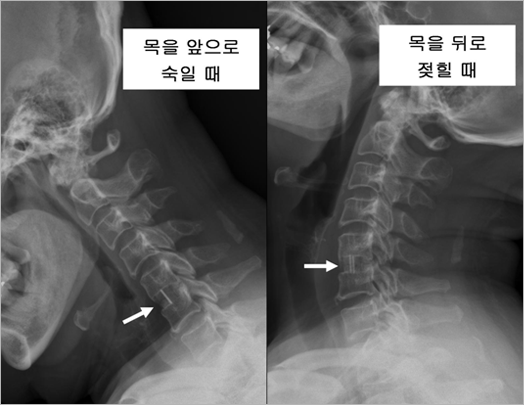

| 추간판은 주로 척추를 따라 전달되는 하중과 충격을 완화시켜주는 쿠션 역할을 하기도 하며, 척추체사이에 약간의 움직임을 허용할 수 있는 여유 공간으로서 작용하기도 합니다. 그림 2는 정상인에서 목을 앞으로 숙일 때와 뒤로 젖힐 때 각각 촬영한 엑스레이 사진입니다. |

| • 그림 2 정상인의 경추 엑스레이 |

![]() |

| 하얗게 보이는 부분이 척추체이고, 그 사이에 까맣게 비어있는 것처럼 보이는 공간(화살표)이 바로 추간판입니다. 추간판은 말랑말랑한 조직이기 때문에 엑스레이에서는 보이지 않습니다. 언뜻 봐서는 차이를 잘 모르겠지만 목을 앞으로 숙일 때는 척추체 앞부분의 간격이 좁아지고 뒤로 젖힐 때는 넓어지는 것을 관찰할 수 있습니다. 이것은 목의 운동에 따라 추간판의 모양이 변화한다는 것을 의미하며, 거꾸로 말하면 추간판이 변형될 수 있어야 목(경추)의 움직임이 가능하다고 할 수 있습니다. 정상 성인에서는 각 추간판 마디마다 약 10도 정도의 움직임이 가능하다고 알려져 있는데 이것은 추간판이 정상적인 기능을 유지하고 있을 때에만 가능합니다. 추간판은 비록 작지만 구조나 기능, 생리학적인 면에서 매우 복잡한 구조물이어서 현재까지 수많은 의학자와 과학자들이 연구를 계속하고 있으나 아직까지도 그 비밀이 완전히 밝혀지고 있지 않습니다. 다만 최근 목의 운동 중에 생기는 추간판의 변형을 모방해서, 움직임이 가능한 원판 모양의 기계 장치를 개발해 내었는데 이것이 인공디스크이며, 이 중 경추 추간판에 맞게 만든 것이 경추 인공디스크입니다. 경추 인공디스크는 한 가지 형태만 있는 것이 아닙니다. 주로 유럽과 미국에서 수많은 모델의 제품이 개발되었는데, 어느 정도 안정성이 입증되어 우리나라에서 실제 사용되고 있는 것은 약 10여종에 달합니다(그림 3). 하지만 어떠한 모델이건 기본적인 구조는 거의 동일하다고 할 수 있습니다. 우선 추간판이 제거되고 노출된, 위 아래 척추체의 단면과 접촉하여 단단히 유합될 수 있는 두 개의 판이 있고, 그 사이에 움직임을 만들어 줄 수 있는 "베어링" 구조가 끼어 있습니다. 그림 3을 보시면 쉽게 이해할 수 있을 것입니다. |